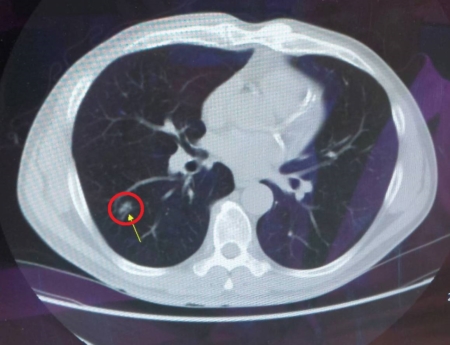

【大紀元2025年05月23日訊】(大紀元記者陳文敏台灣苗栗報導)60歲的江先生本身有吸菸史,平時身體狀況還算不錯,僅因高血壓定期在門診追蹤。在一次回診時,接受醫護人員建議,安排成人健康檢查及肺癌低劑量電腦斷層掃描(LDCT),竟意外發現右下肺葉有一個小腫瘤,因此到胸腔外科持續追蹤。經過兩年的密切觀察,醫師發現江先生的腫瘤有輕微增大跡象,幸好腫瘤尚未擴散,於是建議接受微創胸腔鏡手術切除,術後三天順利出院、恢復狀況良好。

大千綜合醫院胸腔外科醫師楊絡勝表示,早期肺癌的手術主要在於將腫瘤及其周圍部分的肺組織切除,以達到切除病灶、清除癌細胞的目的。由於江先生的腫瘤在早期即被發現,也相對較小,評估適合接受微創手術,術後的切片病理報告顯示為肺癌第一期,只需定期追蹤,讓江先生直呼幸好有接受篩檢,才能及早發現並治療,為他帶來扭轉病情的機會。

肺癌是目前主要的癌症死因之一,由於肺癌早期沒有明顯的症狀,許多病人在確診時已屬晚期,失去手術治癒的機會,因此早期發現是非常重要的關鍵。現行低劑量電腦斷層掃描(LDCT)主要用於肺癌的早期篩檢,可以找出2~3毫米小的結節,並及早接受治療。早期肺癌經醫師評估後,可接受微創胸腔鏡手術,有傷口小、恢復快、疼痛感輕、出血少、併發症發生率低等優點。研究顯示,早期發現並手術切除的病人,五年存活率高達90%以上,且治癒機率較晚期發現的病人更是大幅增加。